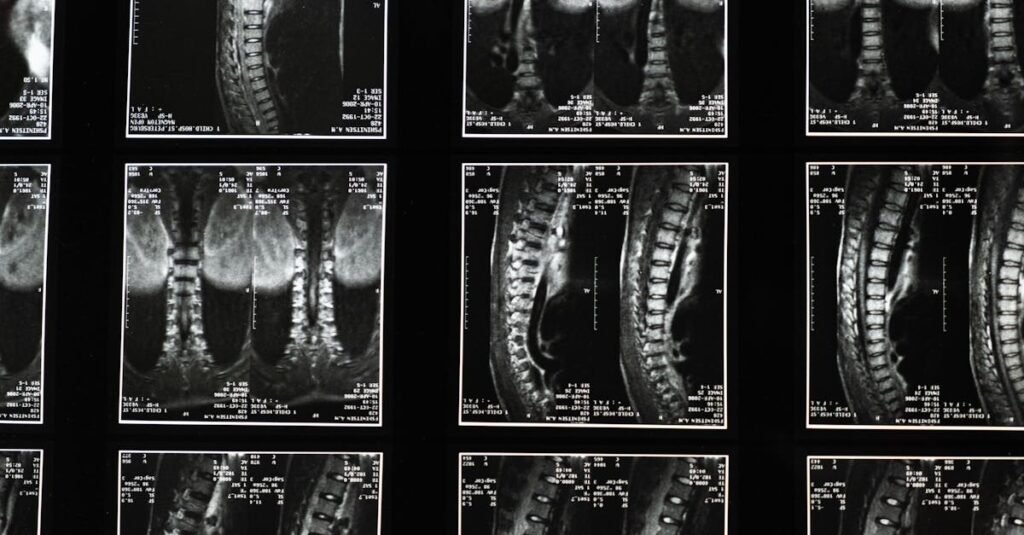

Diagnostic

IRM ou examens cliniques pour évaluer l’état du nerf crural.